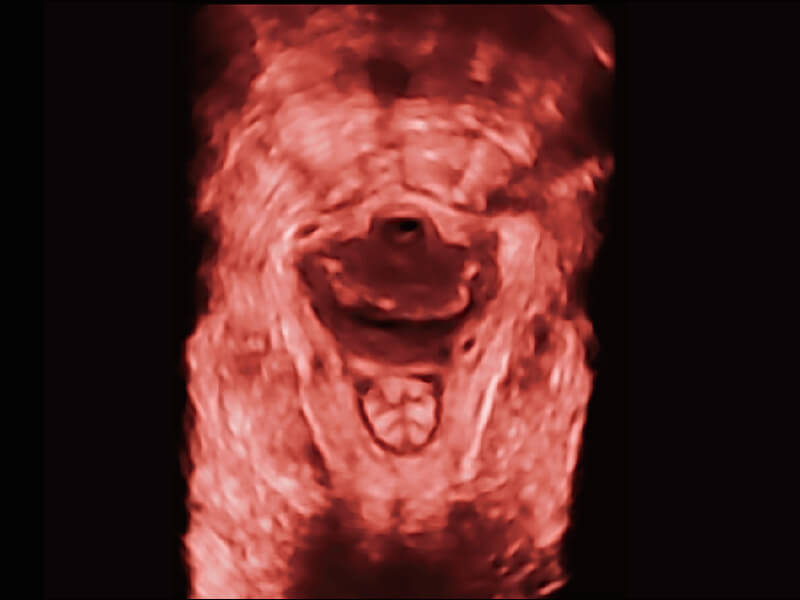

超宽频带技术,为容积成像带来优质的二维图像基础,为您呈现丰富的结构细节,栩栩如生地展示宝宝的宫内形态以及各种组织的立体结构。